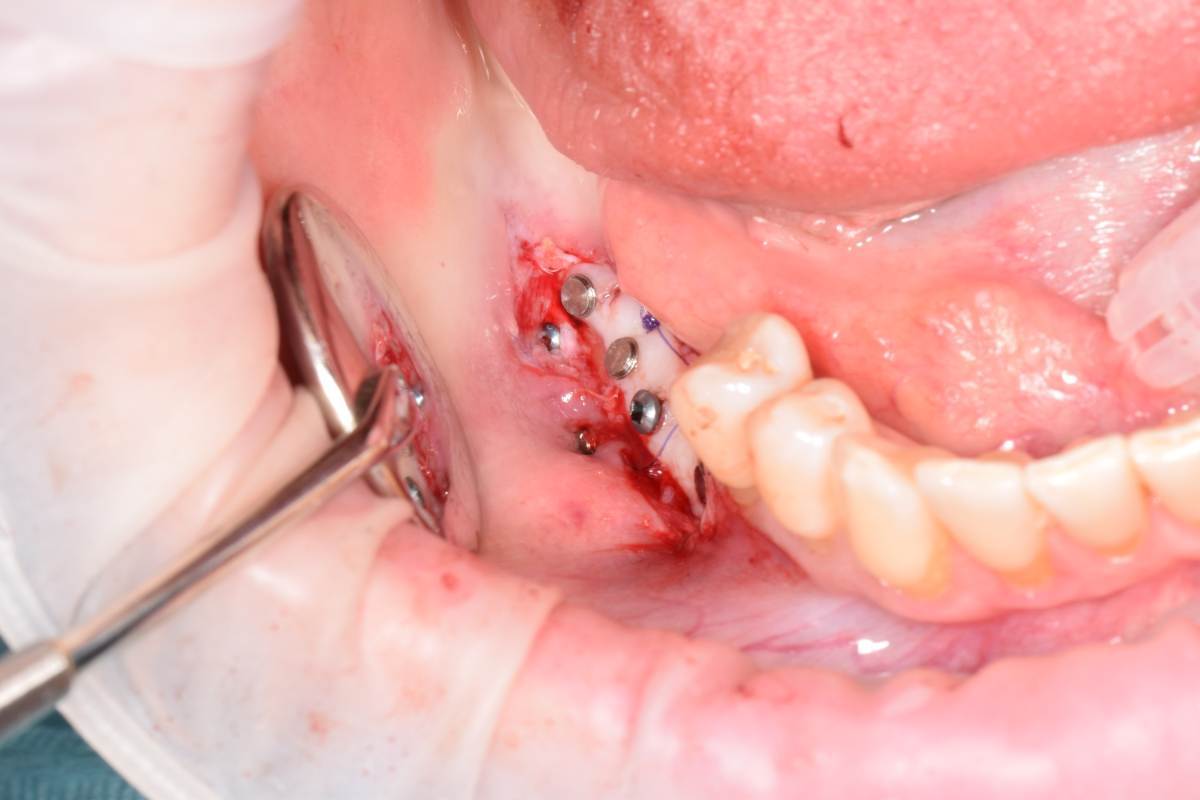

Да, фото есть. Но вспоминаю клин случай, там на первом этапе уже были проблемы.

СдТ по Едранову, видимо получил воспалительный процесс. В результате СДТ усело более чем на 50%.  Потом через 1.5 мес. открытие имплантов и ССТ. Некроз у одного импланта.Думаю связано с неполным ушиванием и ССТ с эпителием. Восстановление слизистой после некроза 2 мес и временное протезирование. Сейчас все выглядит достойно, но лишние нервы.

DSC_0905.JPG.d80af1f969af81edaec8fcb8e56af9dd.JPGDSC_0918.JPG.8053b3712edc335c60fe1603758c57c0.JPGDSC_0961.JPG.d7322462935746ed55516c1f2f016178.JPGDSC_1033.JPG.4e248180e536c308f43b21f90c8d7f39.JPGIMG_20250429_233136.jpg.c4afee93d2d2d38c68fd0335f7814cf2.jpgIMG_20250429_233013.jpg.58a7d5dc49b818431505d37c6561f01e.jpgDSC_0468(1)_d4542c.JPG.507134270c79baa6b79b4eb40f621175.JPG